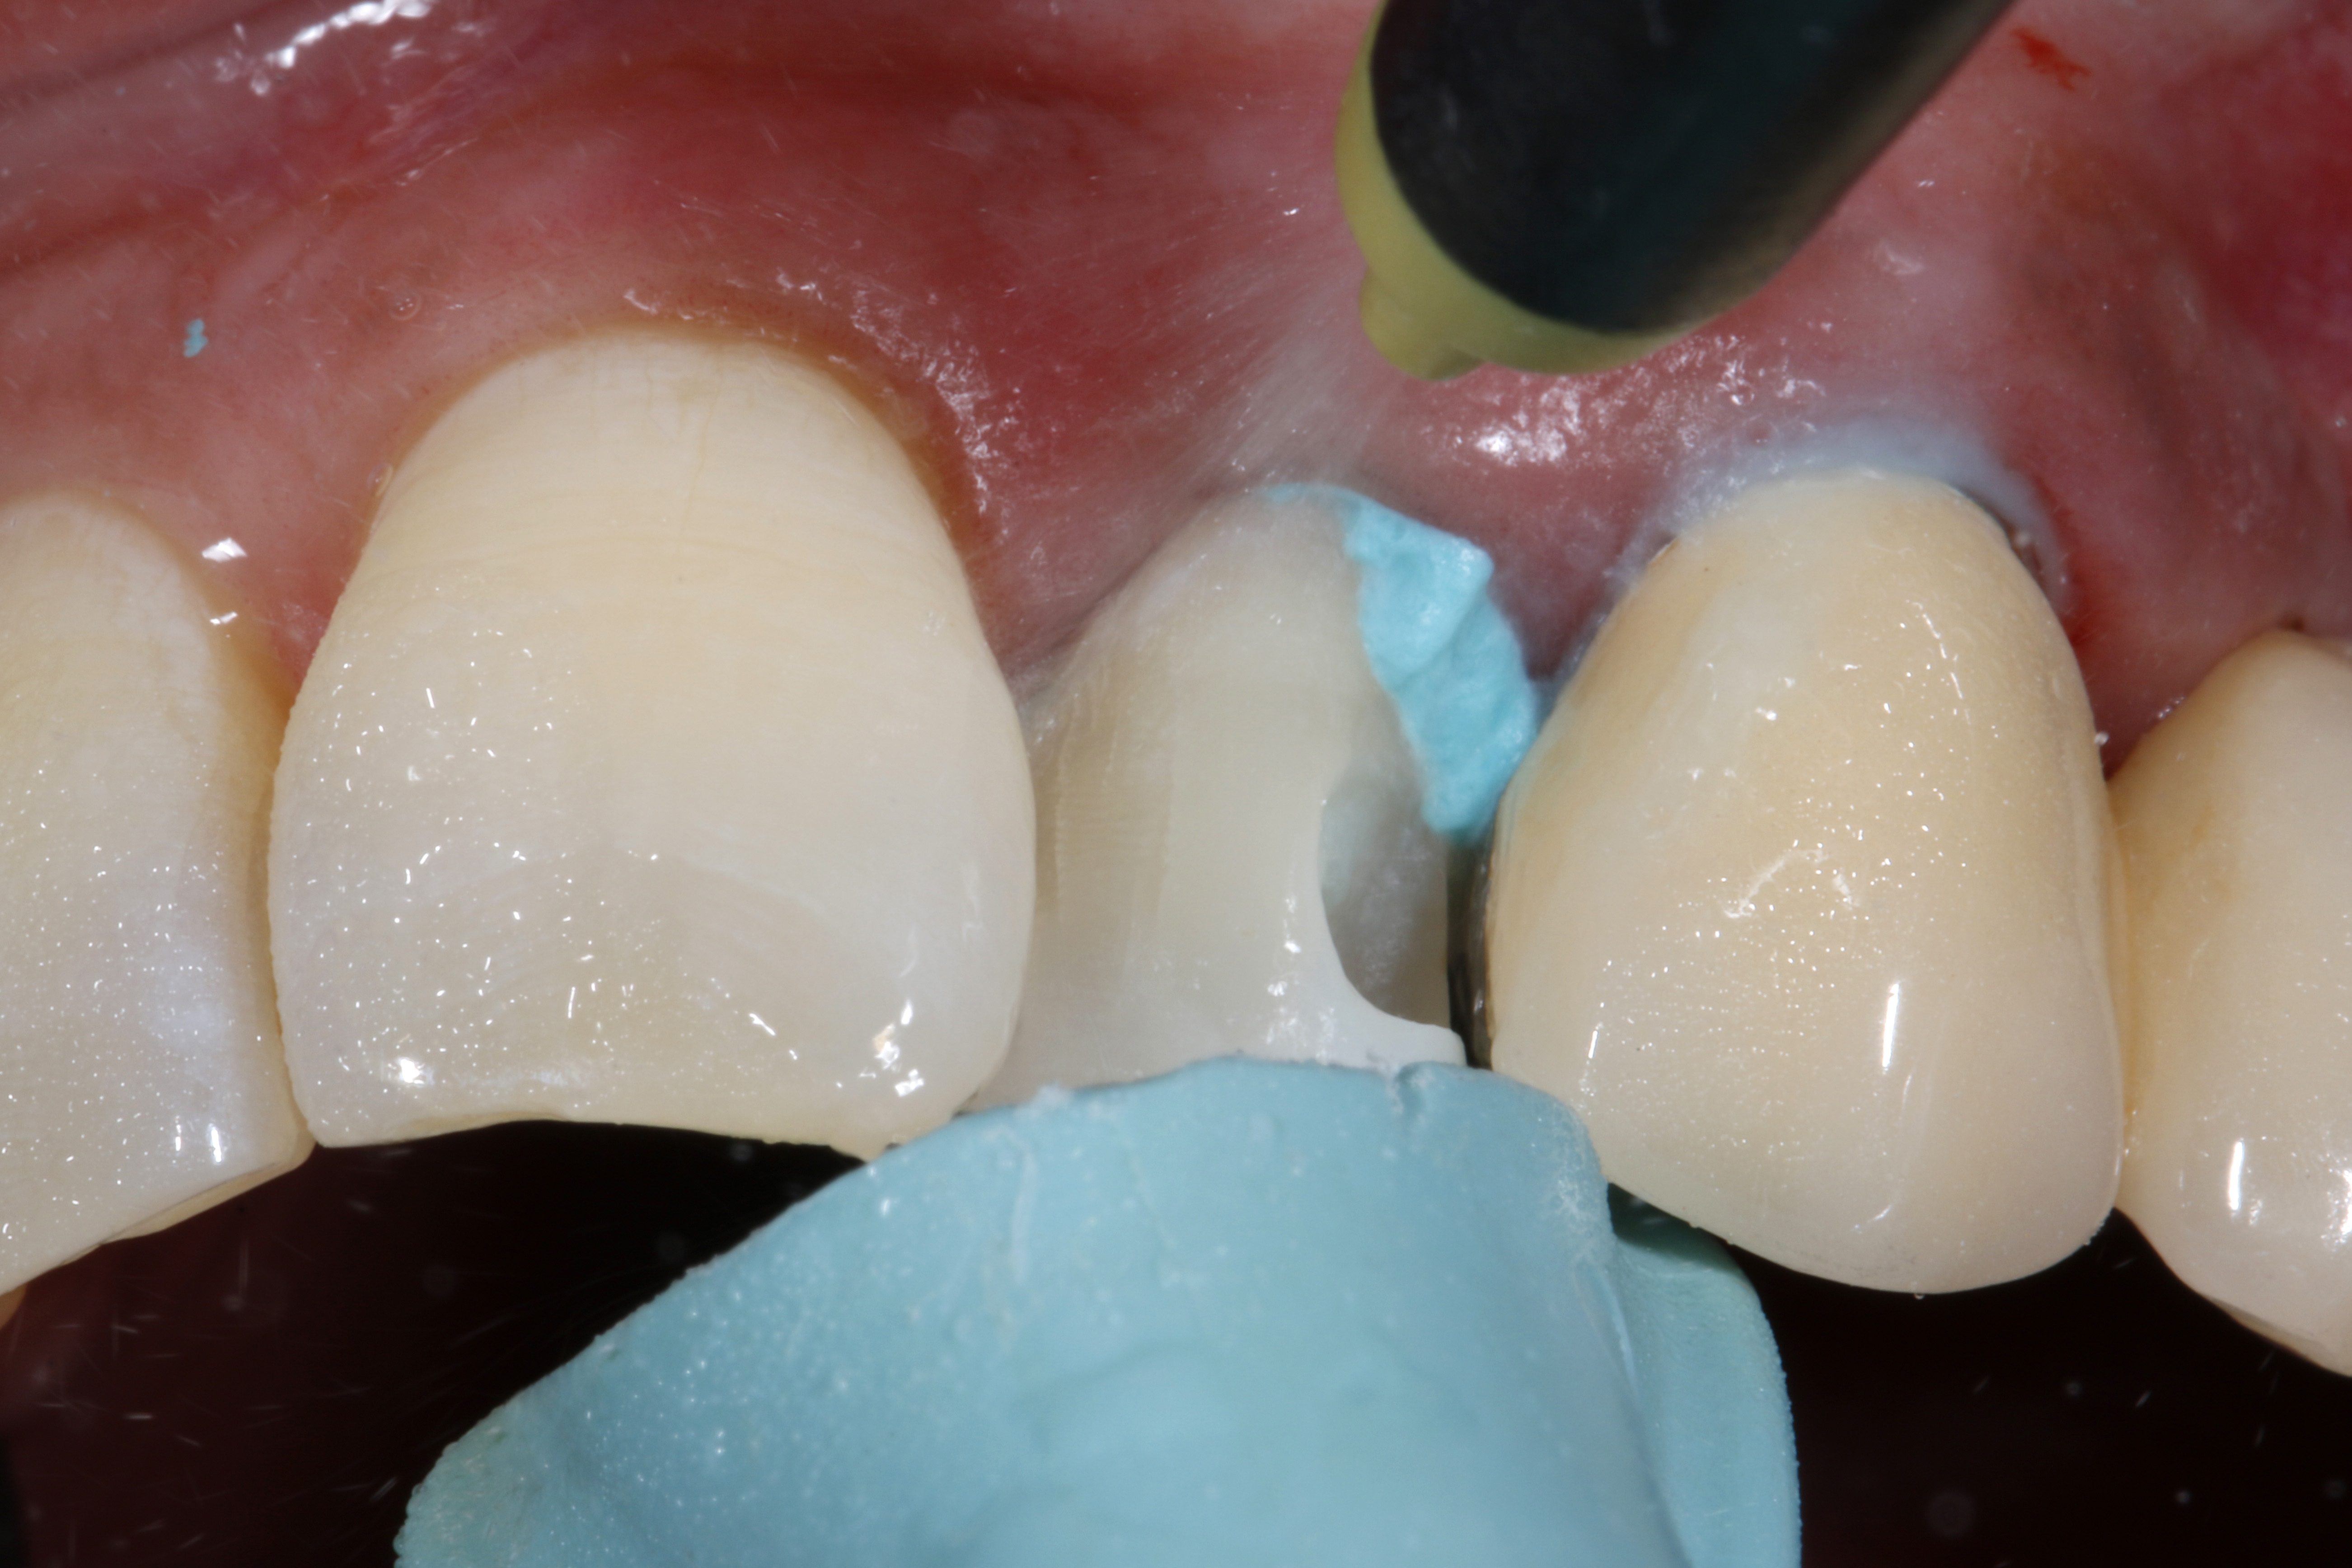

Następnie obszar osuszono sprężonym powietrzem. Miejscowe krwawienie w okolicy dziąseł zatamowano łatwo i skutecznie za pomocą pasty retrakcyjnej zawierającej chlorek glinu i kaolin (ryc. 8). Tylko czyste i suche pole zabiegowe pozwala na dalszą pracę bez zanieczyszczeń. W kolejnym etapie zabezpieczono oba sąsiednie zęby taśmą teflonową (ryc. 9).

Ryc. 8. Krwawienie udało się łatwo i skutecznie zatamować za pomocą pasty retrakcyjnej.

Ryc. 9. Sąsiednie zęby zabezpieczono taśmą teflonową